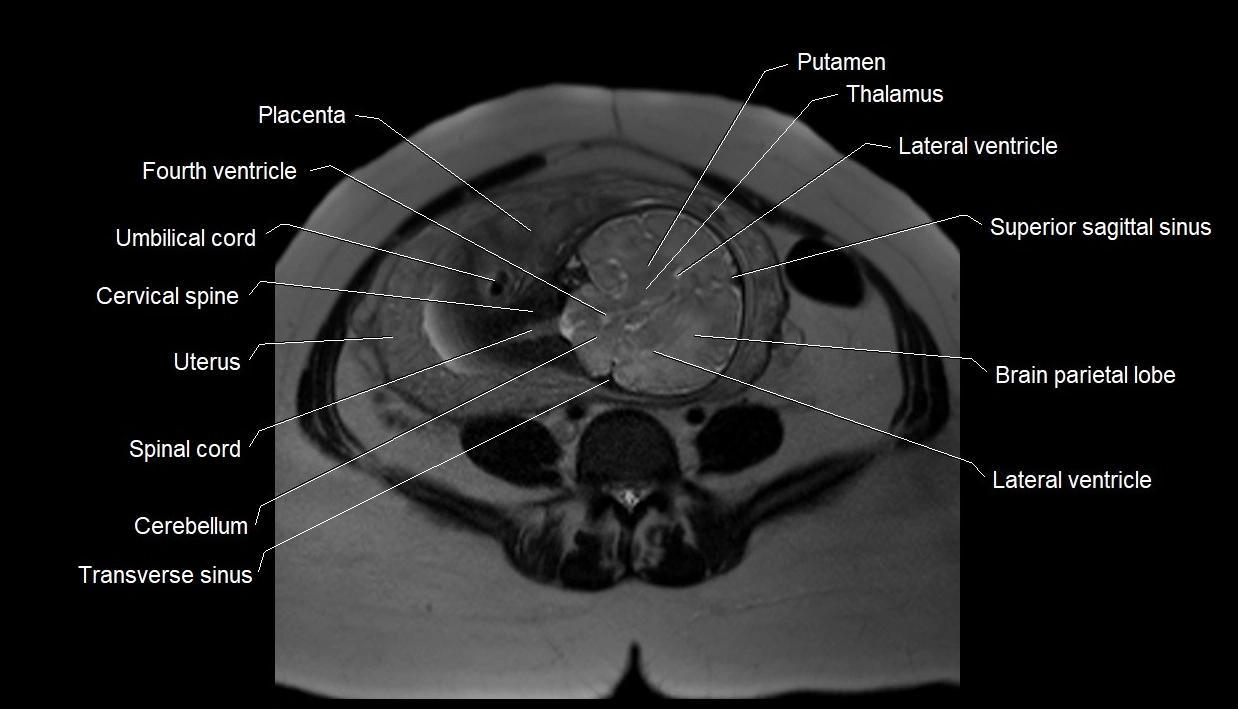

MRI Appearance

T2 HASTE (T2 GRE):

• Amniotic fluid shows very bright hyperintense signal

• Provides natural contrast against fetus and placenta

• Small particles (vernix) may appear as scattered hypointense foci within bright fluid

T1 GRE:

• Amniotic fluid shows low signal intensity (dark)

• Hemorrhage, infection, or proteinaceous content may cause focal or diffuse high signal intensity

MRI image

image